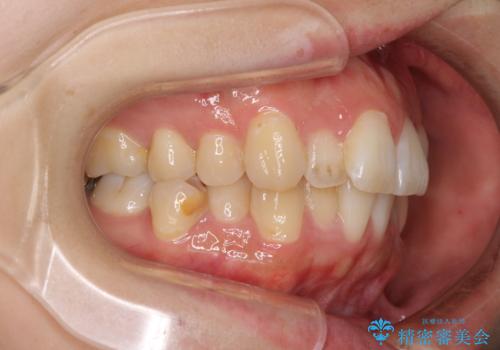

- 前歯のデコボコを気にして来院された患者様です。

非抜歯矯正にて治療を行うと、仕上がりで口元が突出する可能性があったため、小臼歯抜歯での矯正治療を行うこととしました。

上顎は左右の第一小臼歯2本を、下顎は左右の第二小臼歯2本を抜歯して、口元が突出しないようにしながら、奥歯の咬み合わせを改善していく治療計画としました。